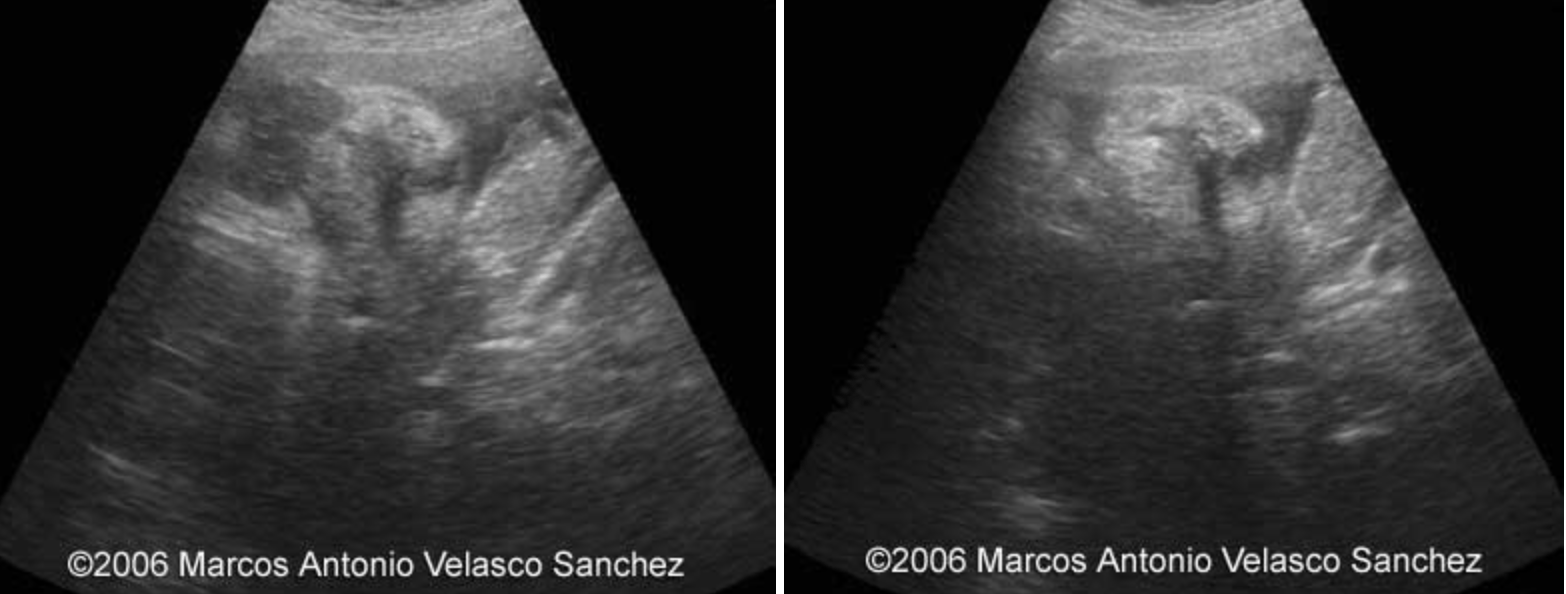

lips

Lips of the fetus